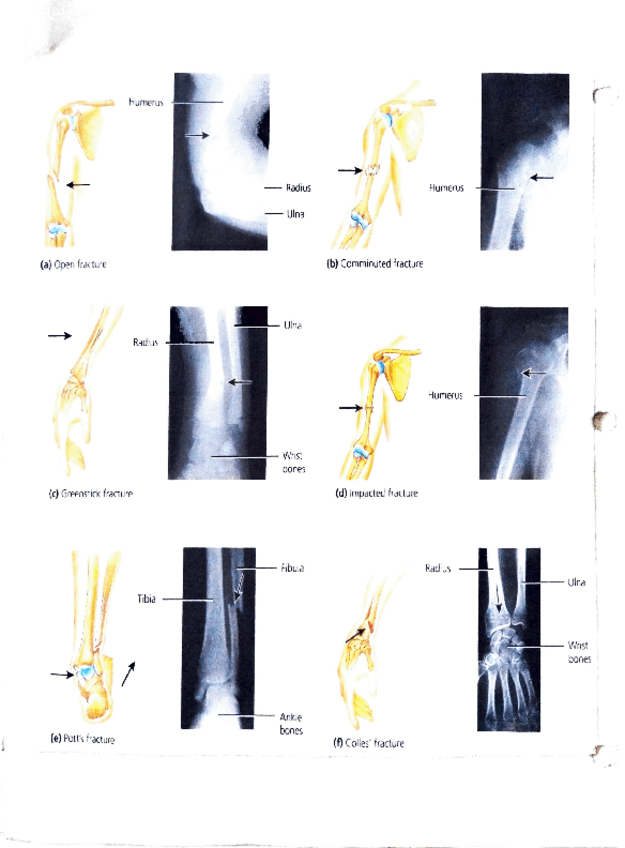

He publicado nuevos apuntes de 1º Estructura y Función Humana: sistema-Esqueletico.pdf

2 páginas

He publicado nuevos apuntes de 1º Estructura y Función Humana: Sistema-esqueletico-.pdf

7 páginas